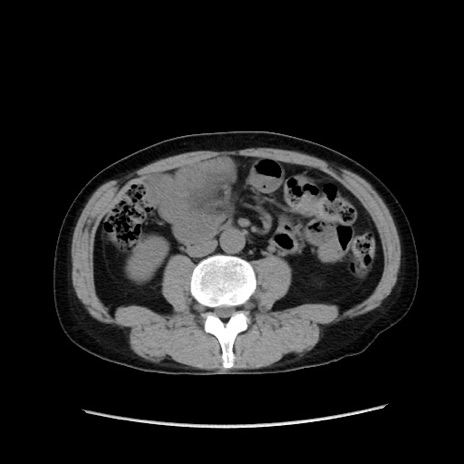

冠状断像

症例37(横断像)

【症例】40歳代 男性

【主訴】腹痛

【現病歴】4時間ほど前に電車に乗車中に臍部上より腹痛出現。徐々に増悪し起立困難となり、救急外来受診。生ものは数日食べていない。今朝お雑煮を食べた。

【身体所見】BT 36.8℃、BP 117/84mmHg、HR 91/min、SpO2 97%、苦悶様、腹部:臍上部広範囲圧痛あり、反跳痛±

【データ】WBC 8100、CRP 0.03